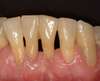

Cas clinique 3: trous noirs

1 sourire initial

13-sourire à 2 mois

Le sourire est retrouvé avec une technique conservatrice qui préserve au maximum les dents, des composites de restauration permettent de redessiner le contour et de faire disparaître les trous noirs tout en préservant la santé des gencives.